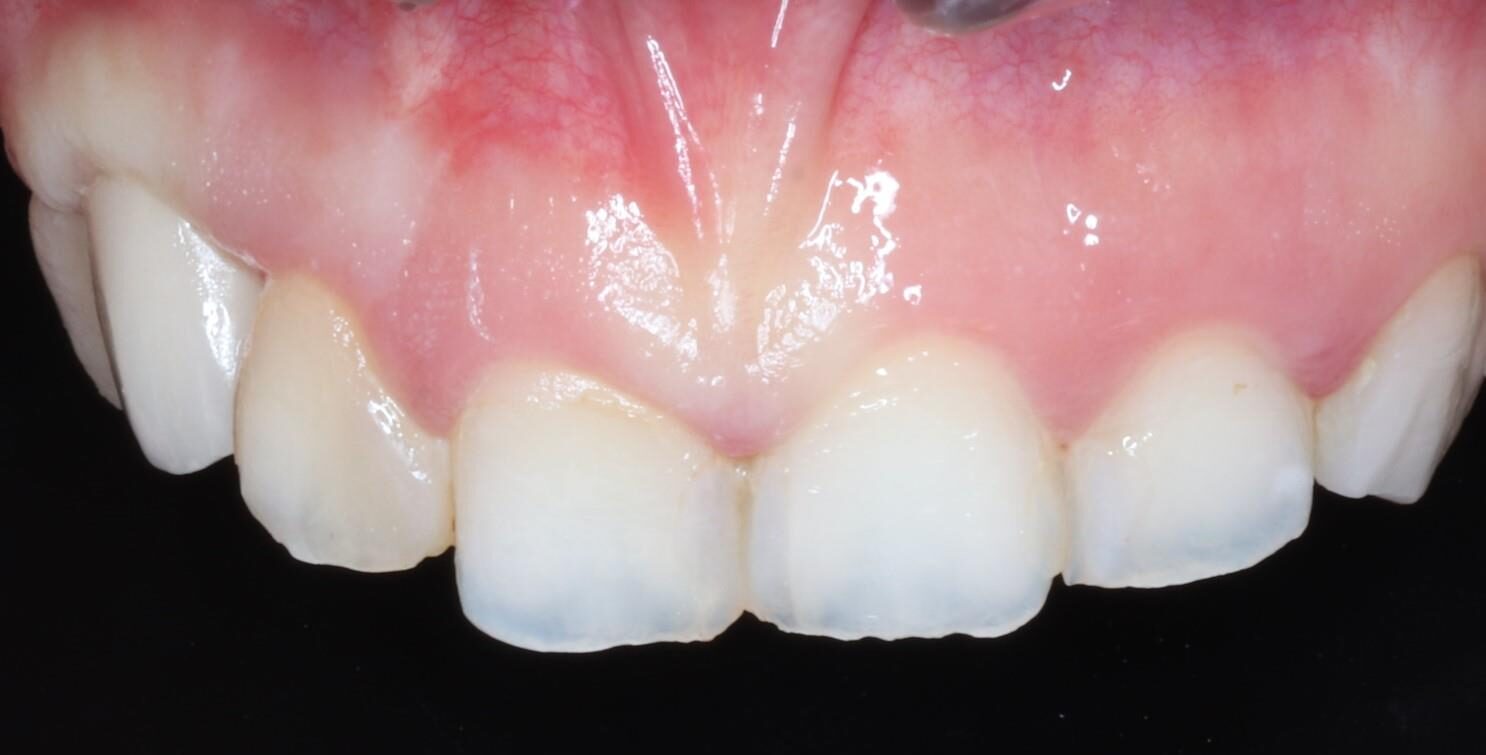

症例12

30代 男性 前歯が折れてしまった。

術前正面観

術後正面観

| 主訴 | 前歯の差し歯が折れてしまい、腫れて痛みがある。できるだけ隣の歯を傷つけずに治したい。 |

|---|---|

| 年代・性別 | 30代 男性 |

| 治療部位 | 上顎左側 1 |

| 治療費用 | インプラント手術料 300,000円 |

| 手術回数 | 1回 |

| 治療期間 | 6ヶ月 |

| 手術時間 | 90分 |

| 治療回数 | 4回 |